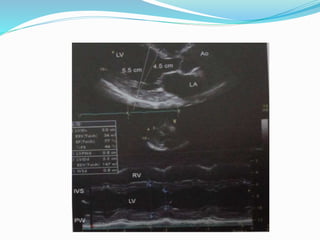

M-mode at Left Ventricle

RVWT

RVIDd

IVSd

LVIDd

LVPWd

IVS excursion

IVSs

LVIDs

LVPWs

LVPW excursion

LV M-mode parameters

range

 Ventricular end-diastolic dimension- 37 to 56mm

 Ventricular end-systolic dimension- 26 to 36mm

 LV diastolic IVS thickness- 7to 11mm

 IVS excursion – 6 to 11mm

 IVS % thickening- 27 to 70%

 LV posterior diastolic wall thickness- 7 to 11mm

 LVPW excursion- 9 to 14mm

 LVPW % thickening- 25 to 80%

 %FS- 28-41%

 EF- 48-78%

LV parameters….

 Stroke volume- 75 to 100cc

 Cardiac output- 4 to 8L/min

 Cardiac index- 2.4 to 4.2L/min/m2

 LV mass- male< 294gm; female<198gm

 Mitral valve EF slope- 50 to 150mm/sec

 DE Excursion- 15 to 25 mm

 Mitral valve E-point septal seperation- <7mm